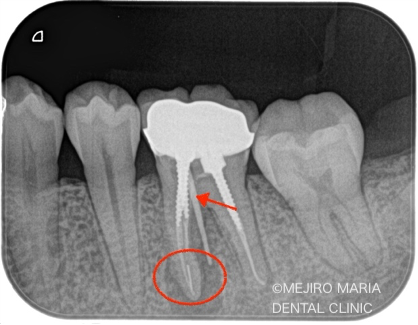

患者様は、数年前にひどい虫歯のために根管治療を受けておられましたが、数日前より左下が腫れ始め、瘻孔(フィステル/溜まった膿を排出する穴)ができたと来院されました。

レントゲンで診査すると、左下6番(第一大臼歯)の近心根(歯の根のより中心に近い部分)に根尖性歯周炎が確認でき、腫脹の原因は根尖性歯周炎であると診断しました。

また、同じ部位の根尖に、透過性の異なる充填物(赤丸)が確認できました。これは、以前の根管治療で使用していた器具が根管内で折れて、そのまま取り残されている状態です。

このように、治療中に折れた器具のことを歯科では「破折ファイル」と言い、トラブルケースの1つとして扱われます。このように細く長い根管で破折したファイルは、再治療の際に根管を洗浄するための器具の到達を困難にし、また、破折ファイルを除去するための器具のアプローチも難しいため、結果として根尖部の洗浄が不十分になってしまいます。